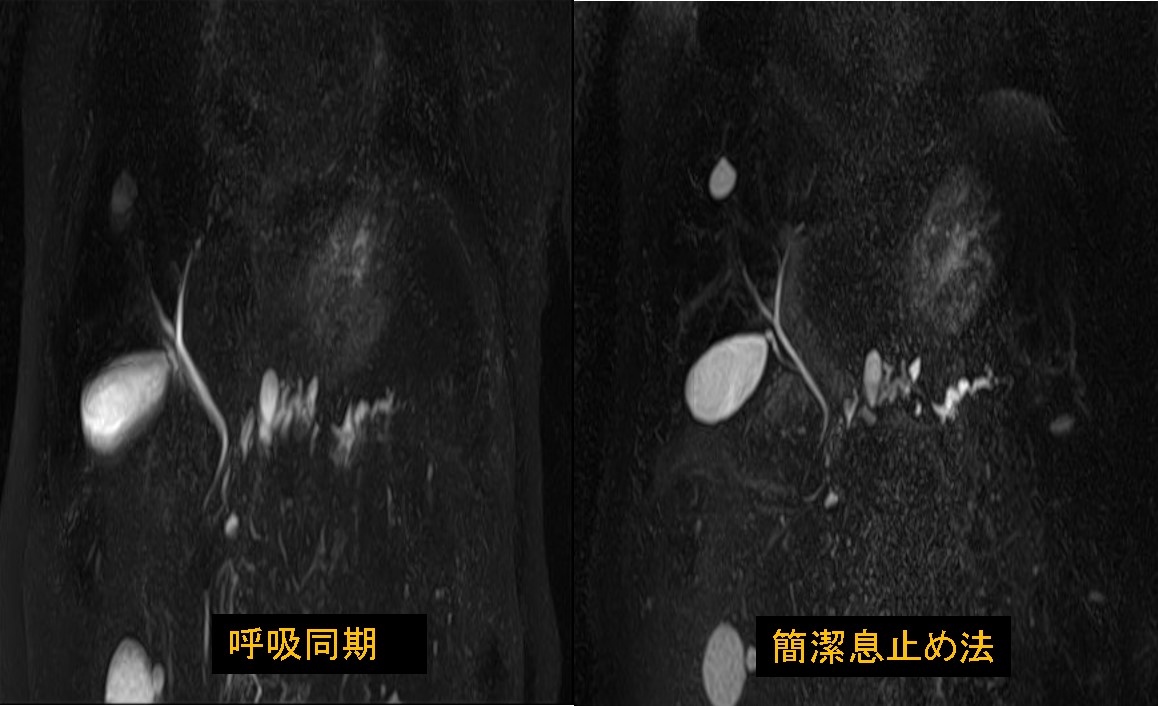

はじめまして、初投稿をさせて頂く獨協医科大学越谷病院 放射線部 大橋一範です。 今回、磁化率アーチファクトの抑制テクニックであるWARPアプリケーションについて語りたい思います。初代WARPアプリケーションではView Angle Tilting(以下、VAT)法を使用しています。